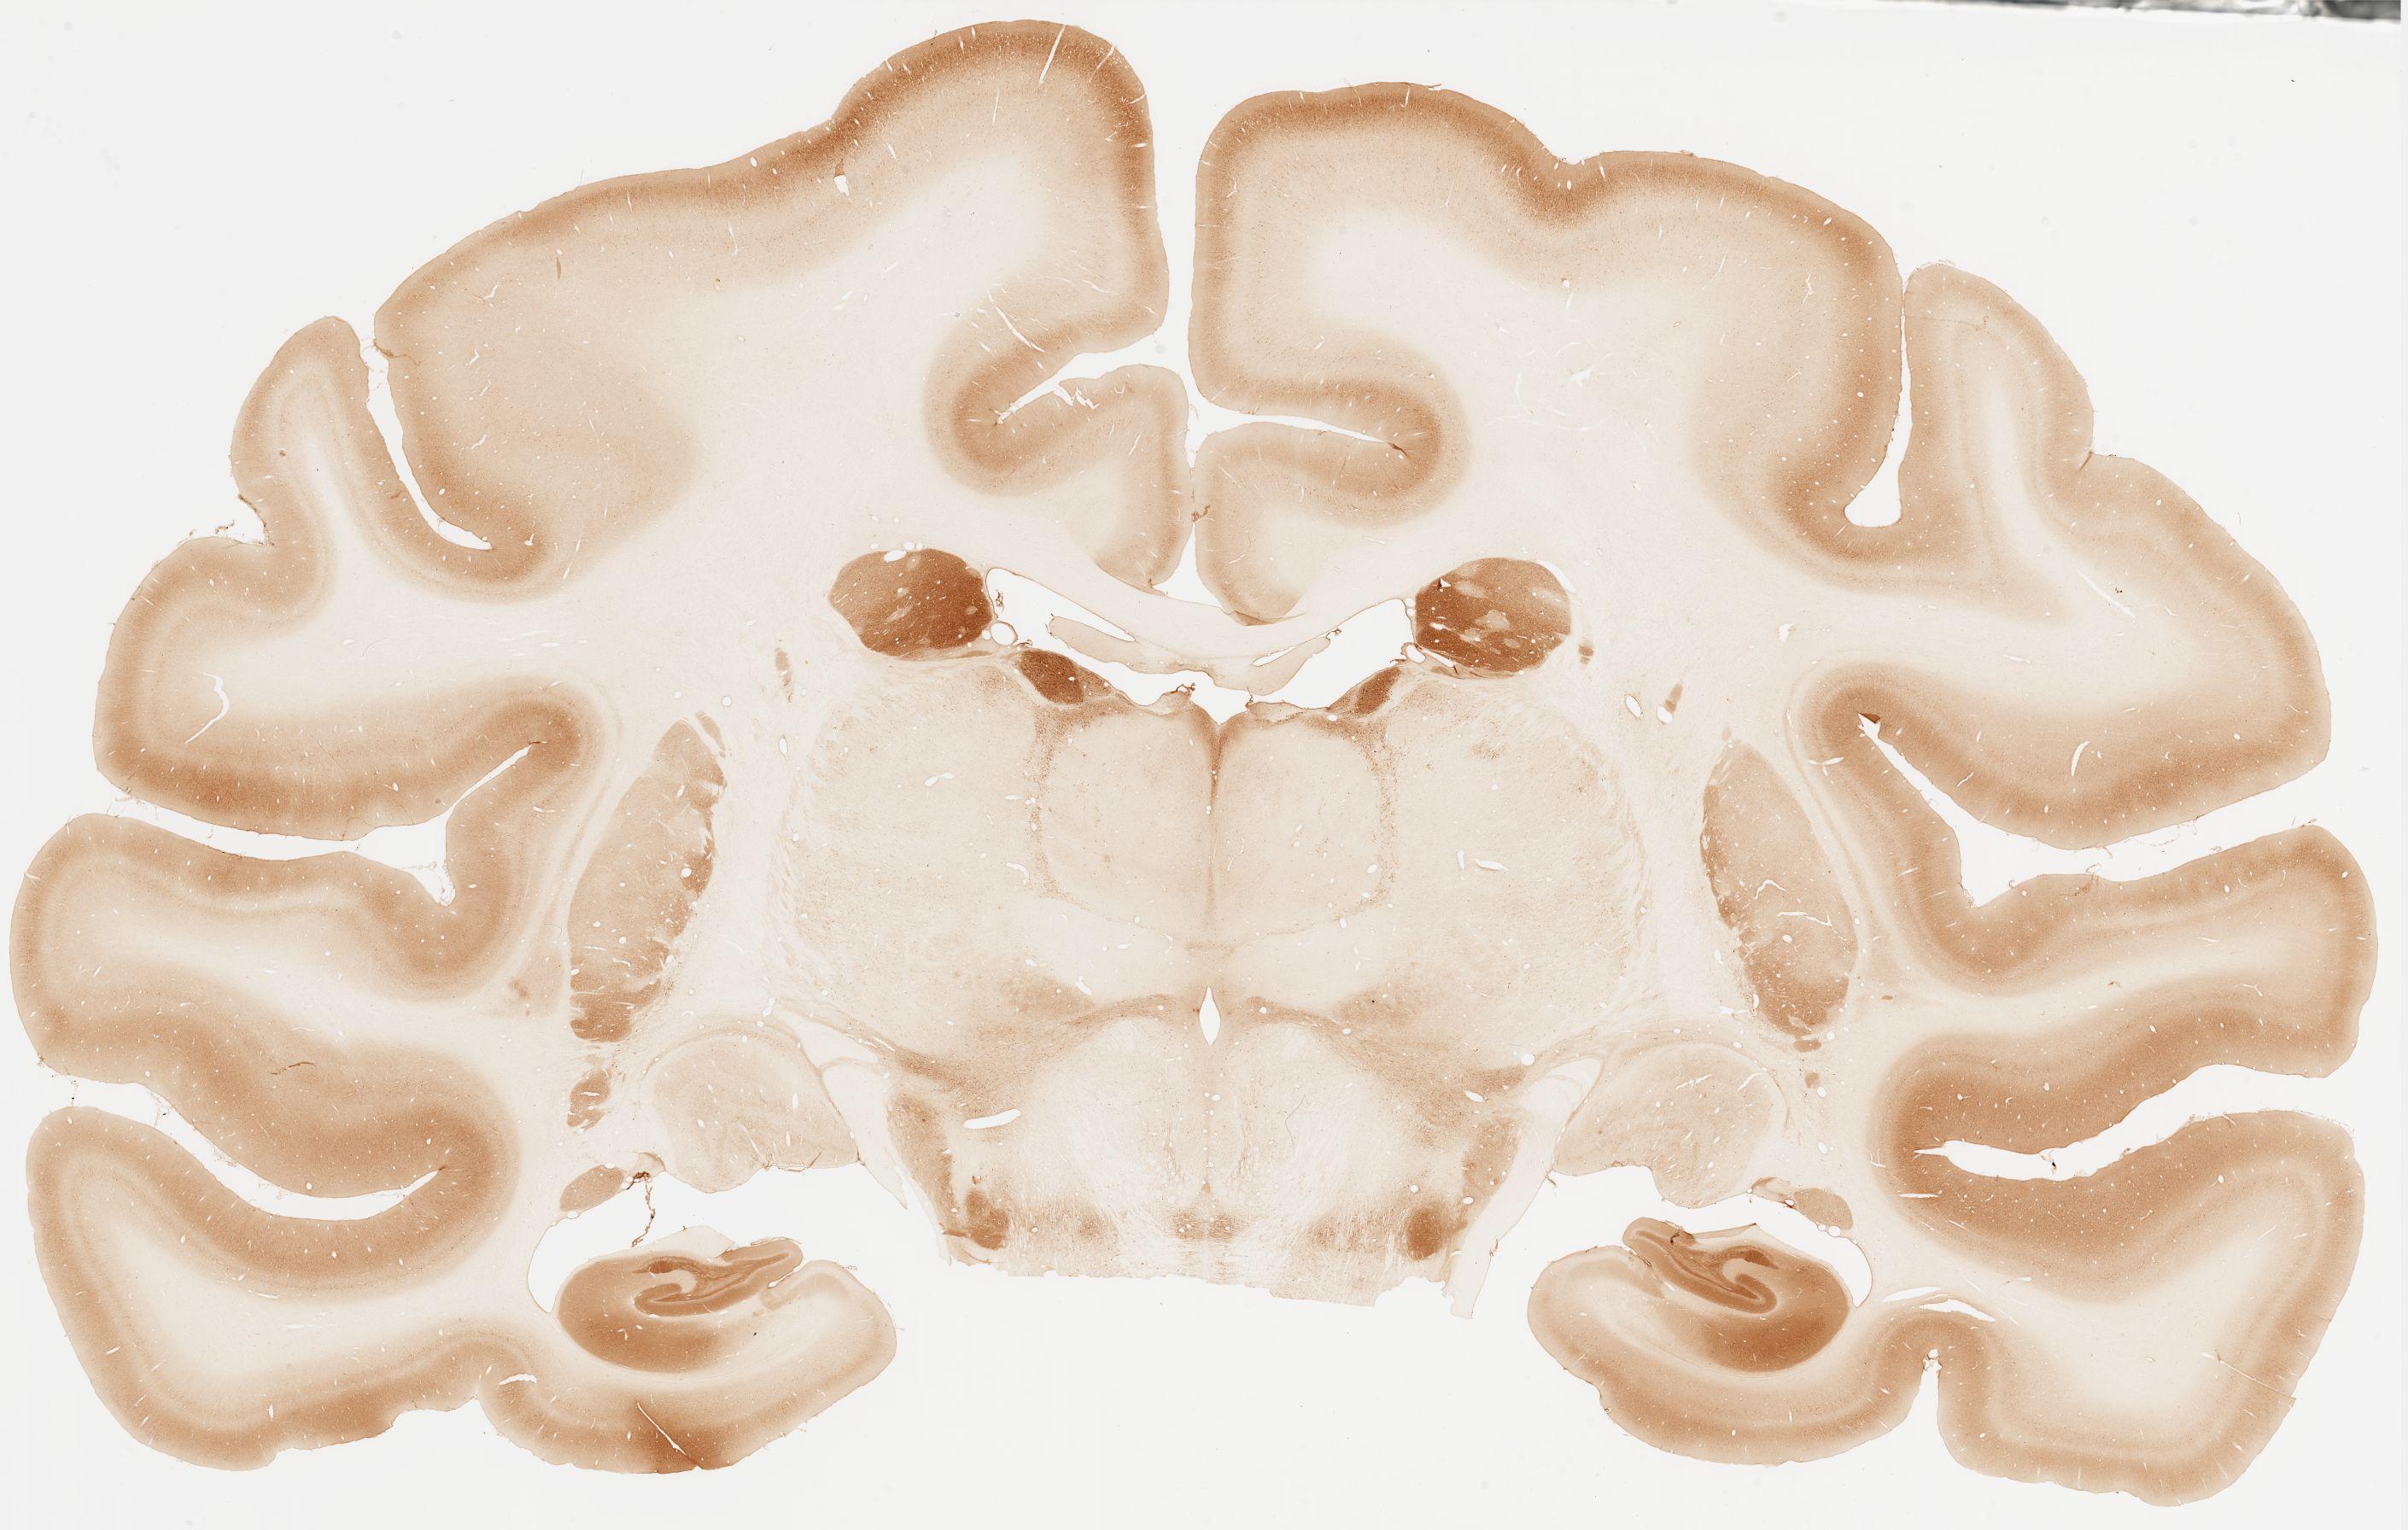

Datasets -> Macaca Fascicularis -> Calb, (Calbindin), coronal, immuno, Whole-Brain, adult

[ Metadata ]   ·   Source: Edward G. Jones

thumbnail

107